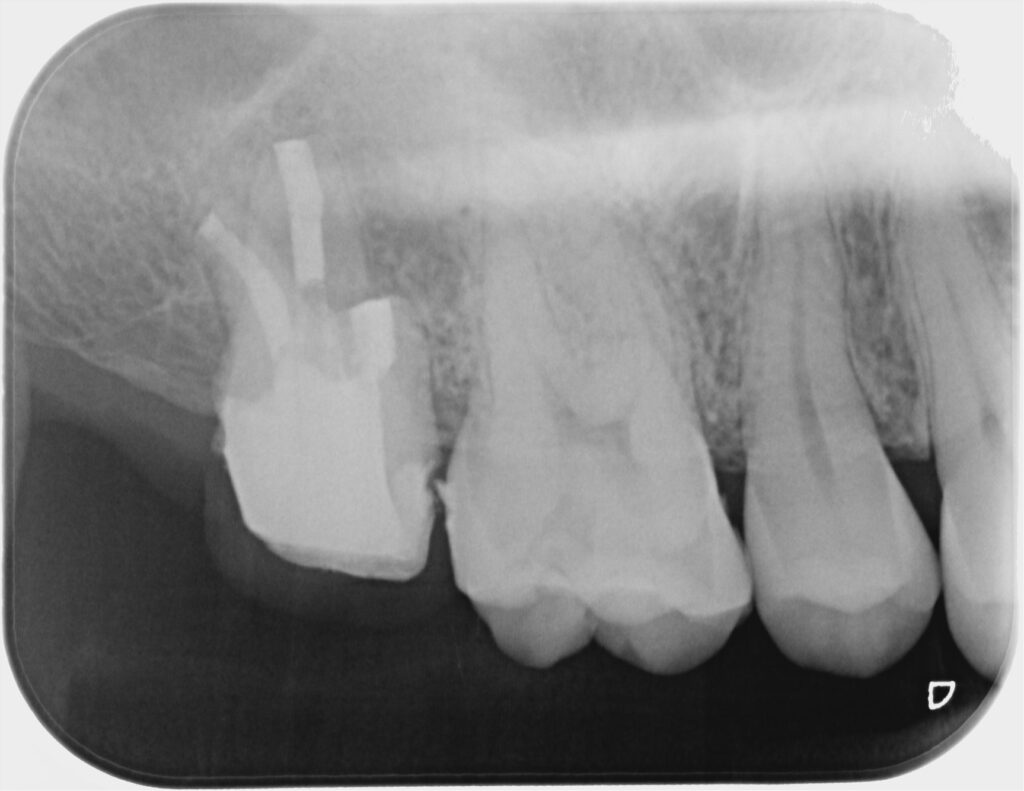

■ 治療内容<意図的再植>

- 口腔内で、修復物の除去、コアビルドアップ

- 歯根膜を損傷しないよう慎重に抜歯

- 口外時間を最小限に管理

- 根尖部の感染組織の除去

- 逆根管充填(MTA使用)

- 速やかに再植

すべてマイクロスコープ下で精密に処置を行っています。